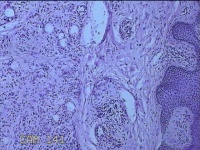

右侧头部息肉结节

性别

男

年龄

39岁

临床诊断

头皮良性肿瘤

一般病史

发现右侧头部息肉结节20余年。

标本名称

右侧头部息肉组织

大体所见

灰白暗红色组织1.2x1x0.8cm一块,表面带梭形皮肤1.2x0.8cm,皮下见结节1.2x0.9x0.3cm一个,切开结节呈实性,切面灰白暗红色,质软。